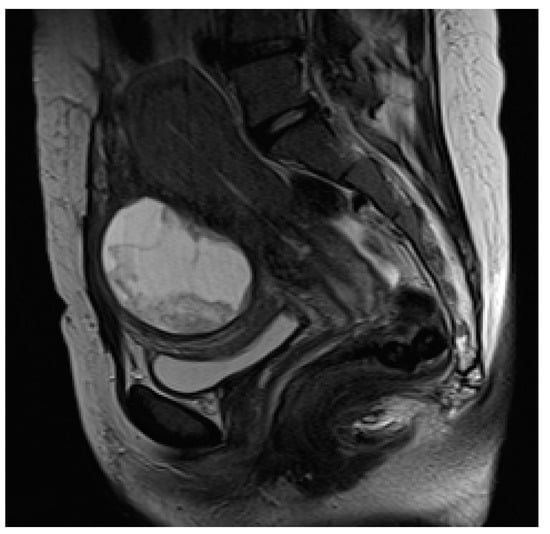

In peripartum and during delivery, the acute clinical presentation of UR obviates the need for diagnostic imaging, which is most helpful when this complication occurs earlier in the pregnancy. US is the first method of choice, owing to its availability, cost effectiveness, and lack of ionizing radiation. While transabdominal US provides a wider field of view (FOV) and better general evaluation of the pregnant status, transvaginal US allows more accurate assessment of the reproductive system [88]. In expert hands, US may depict the site of perforation, as an anterior hypo/anechogenic line, extending to the serosa; the uterus appears bulky and empty, while the placenta and fetal parts are located in the abdominal cavity. The ancillary non-specific findings of UR, such as concomitant hemoperitoneum and extrauterine hematoma, are the most commonly detected. On Color Doppler imaging, vascularity at the site of uterine breach may be decreased due to intra-myometrial hematoma [85,89,90]. When US in inconclusive, MRI represents a problem-solving tool with a larger FOV and improved visualization of the uterine wall, helping to diagnose antepartum UR (Figure 5).

On T2-weighted images, the placenta and amniotic sac are hyperintense, whereas the myometrium is isointense to muscle, allowing the detection of the tear itself. The high-contrast-tissue resolution of MRI provides for the depiction of fetal parts and extrauterine membranes. On T1-weighted images, hyperintensity of blood products identifies the hemoperitoneum [4,7,91].

Additionally, MRI is more accurate than US in differentiating UR from other uterine wall defects, such as UD, due to its ability to identify an intact overlying serosal layer. A correct differential diagnosis between UR and UD is crucial for setting up the most suitable treatment: UR requires an emergency caesarean section, whereas UD can be treated conservatively with antibiotics [7,81].